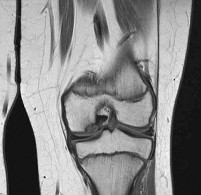

During posterior cruciate ligament (PCL) reconstruction, understanding bundle biomechanics is essential. Which of the following best describes the function and tensioning pattern of the native PCL bundles?

The PCL consists of the larger anterolateral (AL) bundle and the smaller posteromedial (PM) bundle. The AL bundle is lax in extension and becomes tight in flexion, acting as the primary restraint to posterior tibial translation at 90 degrees of knee flexion. Conversely, the PM bundle is tight in extension and lax in flexion.